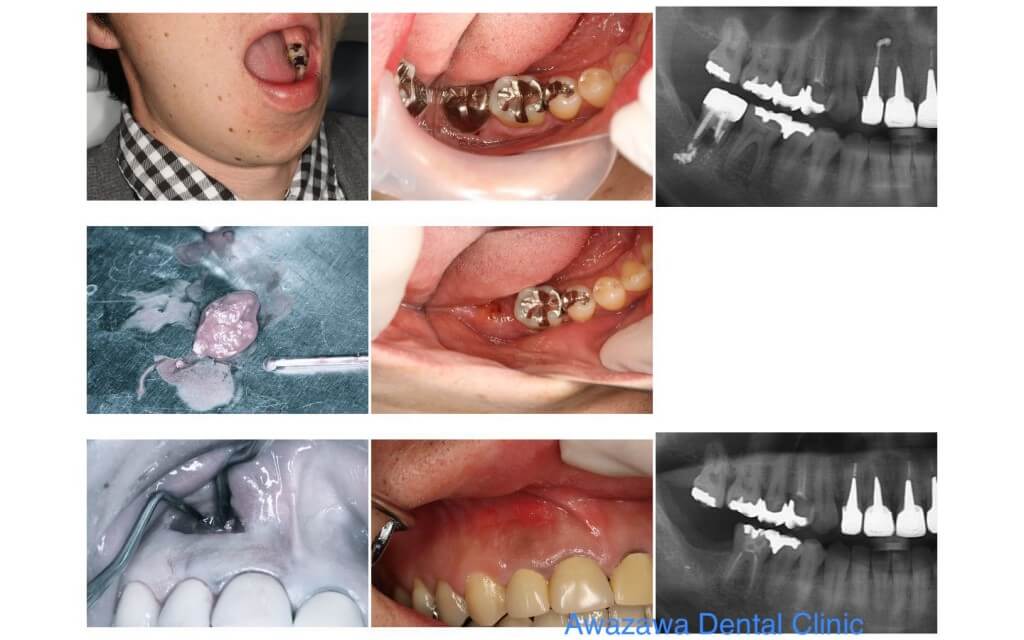

Case.2

下顎右側に水平埋伏智歯が認められます。歯根が2つに分かれ骨を抱き込む様に埋伏していたため、歯冠を切断した後に歯根を分割し抜歯を行いました。 骨を落とす事なく抜歯を行う事で腫れや痛みが少なくて済みます。

Case.3

CT像で下顎に水平埋伏智歯が認められます。歯冠分割、歯根分割を行い抜歯処置を行いました。